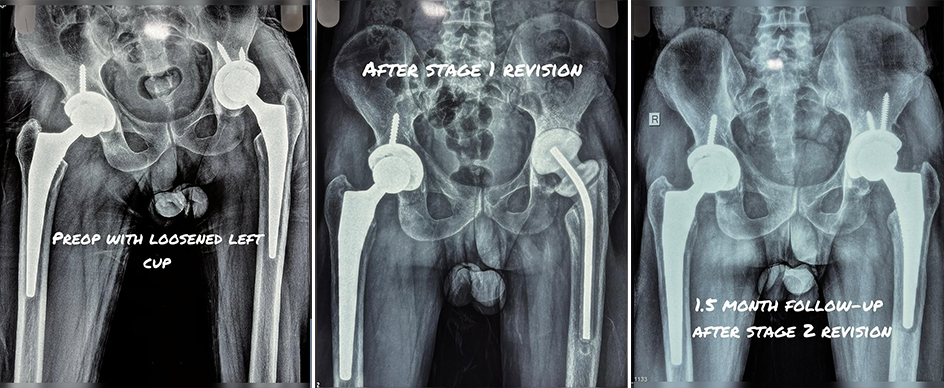

This is the journey of one of our patients who had previously undergone hip replacement on both sides.

Over time, the left hip implant became infected and loose, causing pain and difficulty in walking.

✅ In the first stage, the loose implant was carefully removed, and the hip was prepared for the next step.

✅ In the second stage, a new implant was fixed securely, restoring stability and function.

✅ At just 1.5 months after surgery, the patient is recovering well, walking with confidence, and regaining independence.